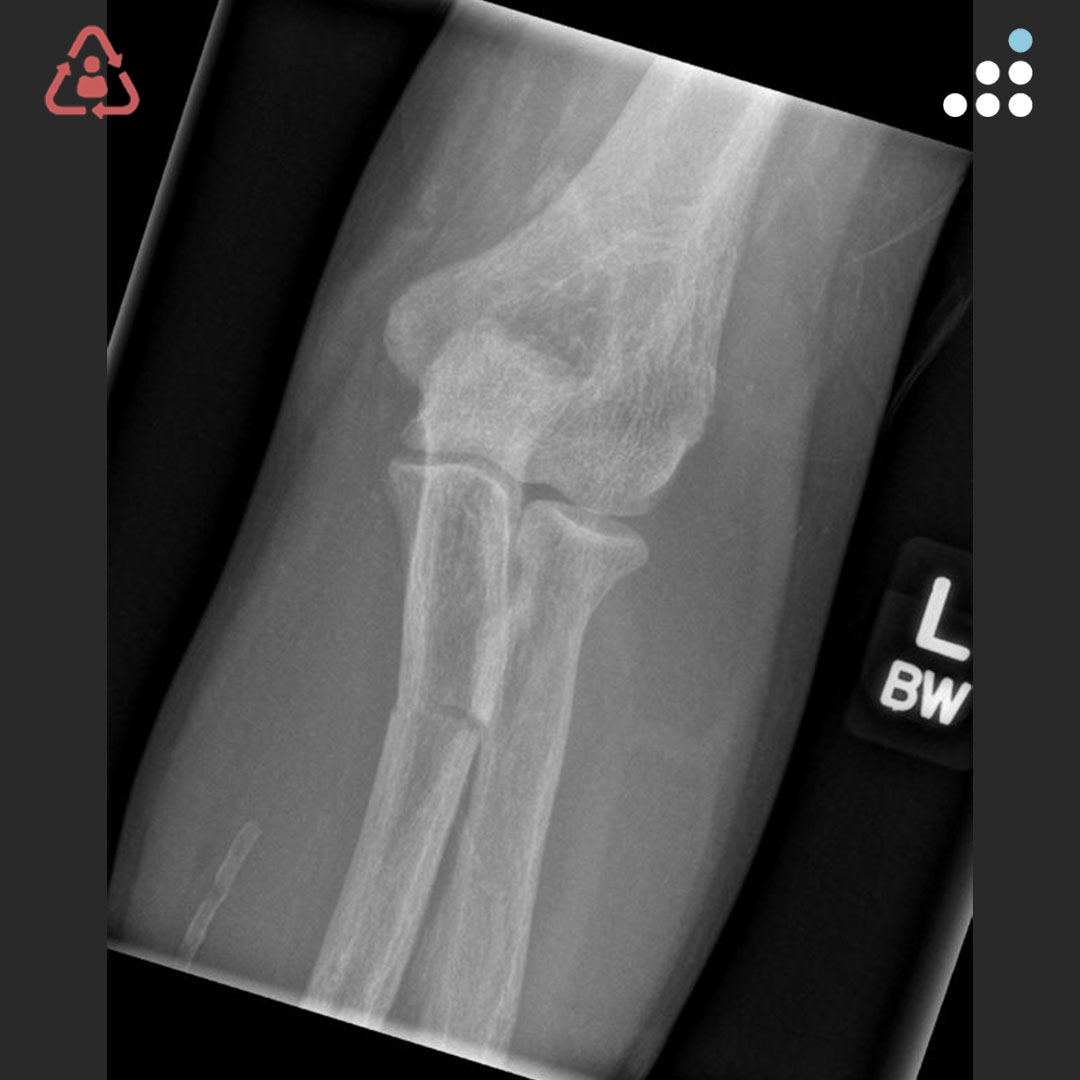

@orthobullets @KPSCALnews @rkh_md @DrMarecek @DeformityDoc @jamesablairMD @FractureDoc @stevemchale @traumaticum @DrFraneNicholas I am concerned about the +Fleck/flake sign. Get MRI or ultrasound to rule out a triceps rupture. If torn, I would perform ORIF and Triceps repair, after restoring the underlying metabolic issues. If the triceps is not torn, then would treat non-operatively.